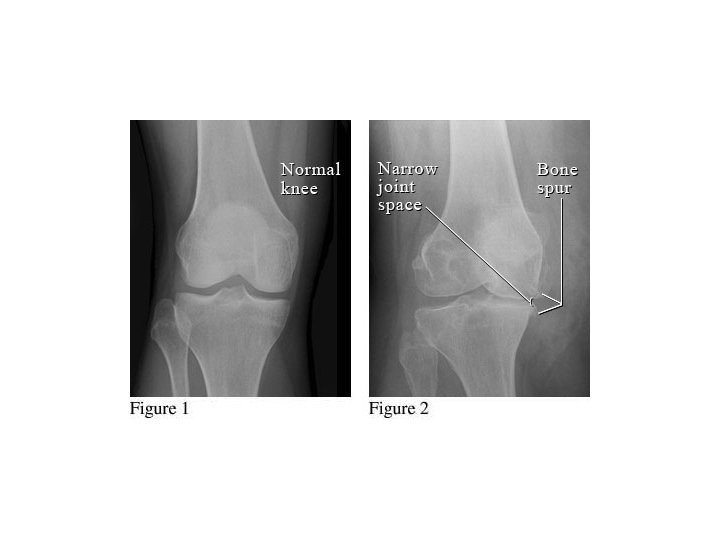

CARTILAGE • Cartilage – joint spaces on x-rays – you cannot actually see cartilage on x-rays • Widening of joint spaces signifies ligamentous injury and/or fractures • Narrowing of joint spaces arthritis